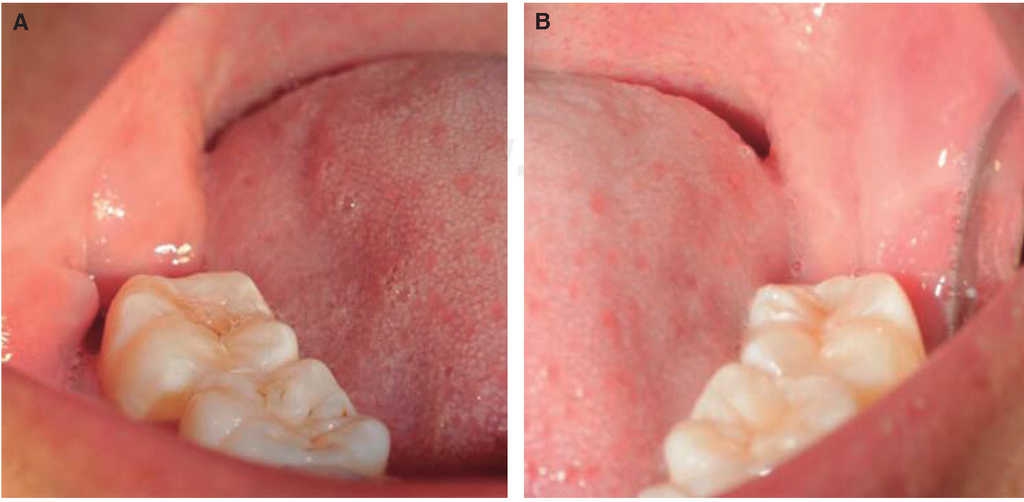

Se observó al octavo día si las heridas estaban abiertas o cerradas (Figura 2). A los 60 días se tomó la radiografía panorámica digital (I-Max Touch 3d Owandy Radiology), la misma que fue procesada en el software RadiAnt DICOM Viewer Versión 2.2.9.10728 mediante la herramienta Ellipse; éste es un software de uso médico odontológico que cuantifica la densidad de contraste imagenológico con la media de valor de píxel o unidades Hounsfield para imágenes de tomografía axial computarizada (Figura 3).16

Figura 2 Herida postquirúrgica a los ocho días. A) Herida derecha abierta. B) Herida izquierda cerrada.

La cicatrización de la herida de tejido gingival se presentó abierta en 26 casos y cerrada en cuatro casos en el lado de control, comparando con 12 heridas abiertas y 18 cerradas en el lado izquierdo en donde fue colocado PRF; teniendo una significancia de p < 0.001 (Figura 6). No se observaron diferencias relacionando por sexo p = 1, tampoco por edad p = 0.49 (Cuadro I).